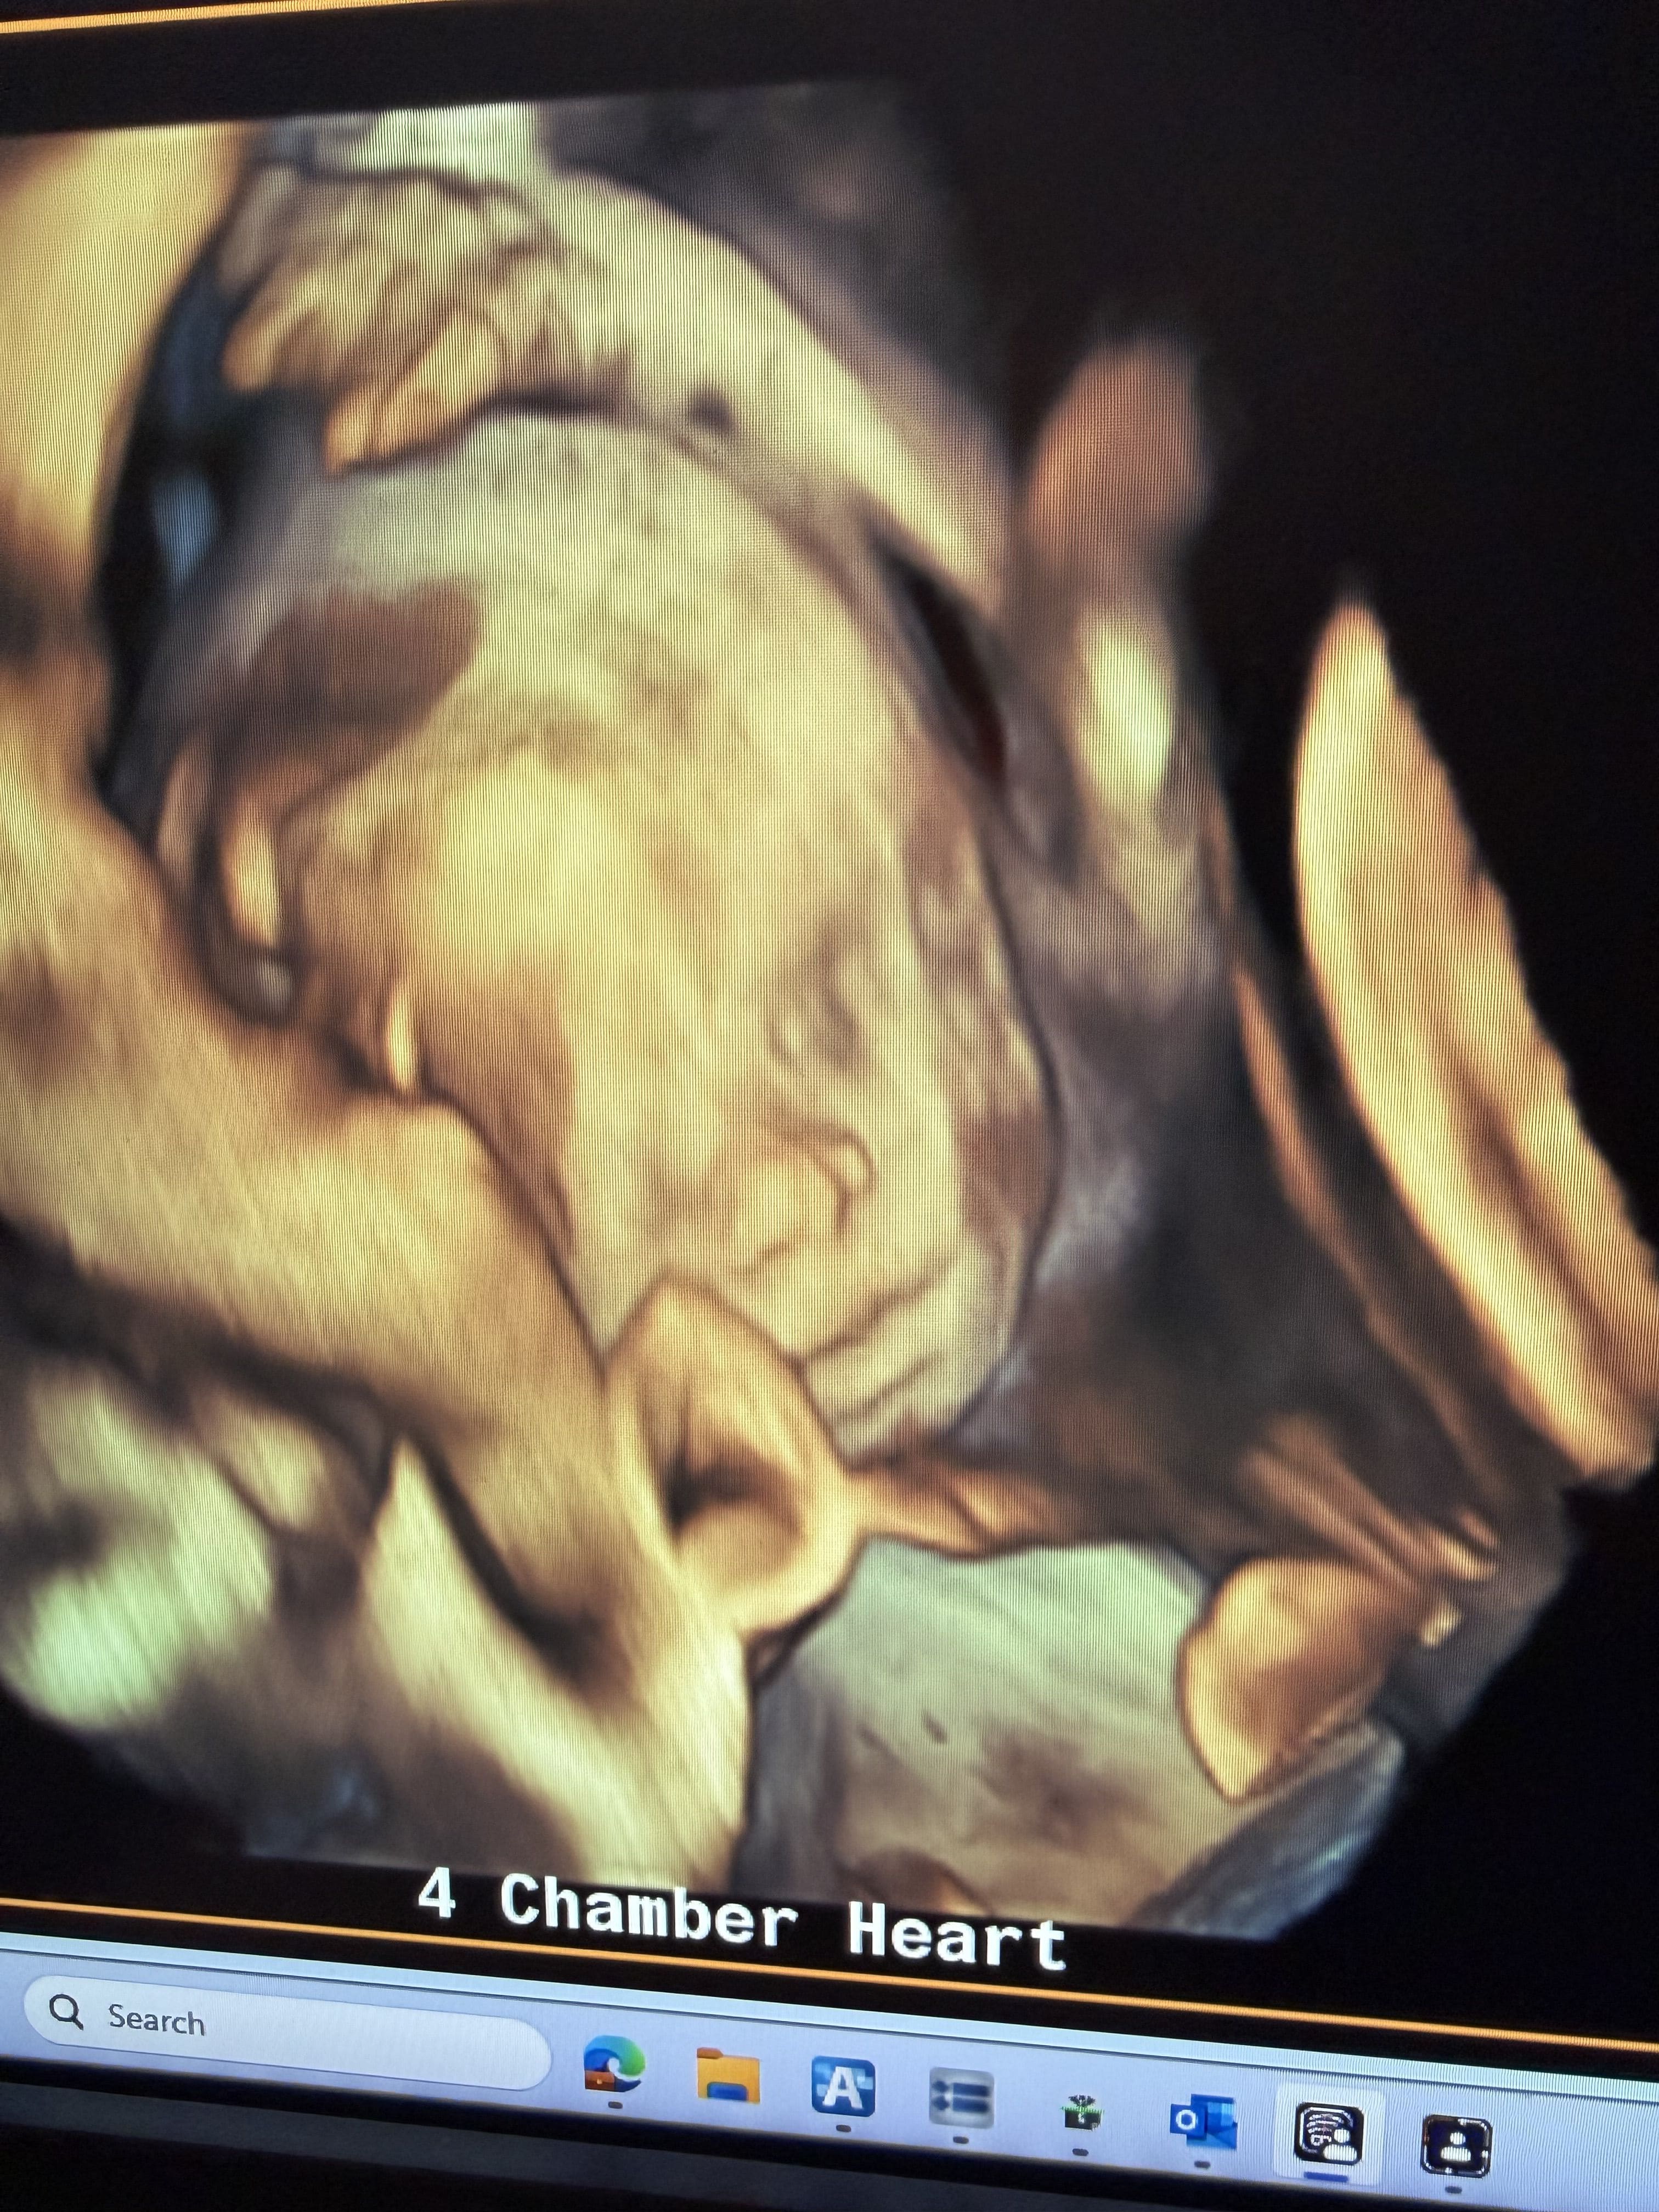

4D Ultrasound